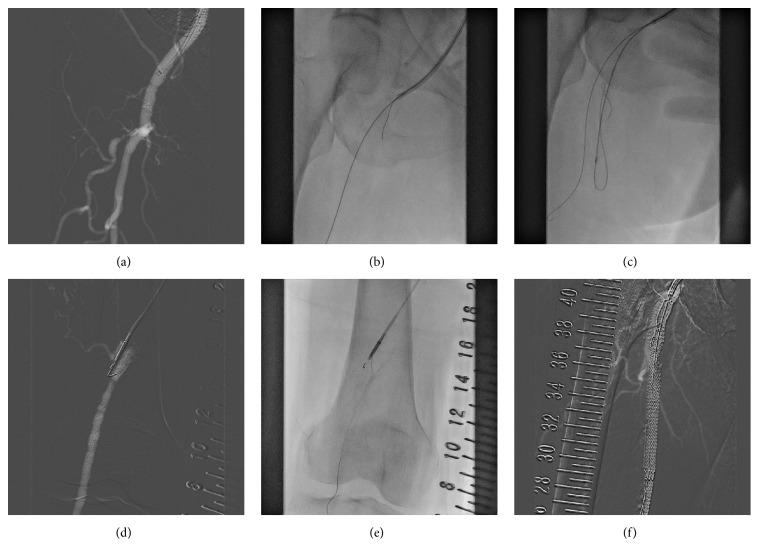

A new reentry device (Outback Elite) system has been available in Japan since June 2016. This new device enables easier treatment of chronic total occlusion (CTO) in the lower extremities. We report a case of a woman in her 70s who underwent revascularization using this new device twice to treat both of her femoropopliteal CTO lesions. She was referred to our hospital complaining of intermittent claudication in both legs. She had a long history of diabetes mellitus complicated with severe chronic kidney disease. Her estimated glomerular filtration rate was <20. She refused surgical revascularization; therefore, we performed our treatment without iodine contrast medium. First, magnetic resonance imaging was performed to confirm that the CTO lesions had caused severe claudication before intervention. Subsequently, the Outback Elite device and carbon dioxide (CO) angiography made it possible to revascularize both of her legs without iodine contrast medium. At 6 months after the procedures, we did not observe exacerbation of claudication in her legs.